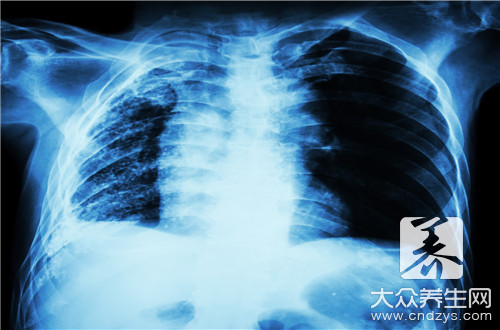

在生活中,潤肺的食物是比較多的,比如豆漿、毛肚血湯以及鴨肉粥等,還有一些中藥材也是可以潤肺的,大家可以在平時適當的吃一些調節肺部。因為肺部我們身體呼吸作用主要的器官,如果肺部功能下降,會影響我們的血液的流通,從而引起支氣管炎等肺部疾病,所以大家可以了解一些潤肺的食物。